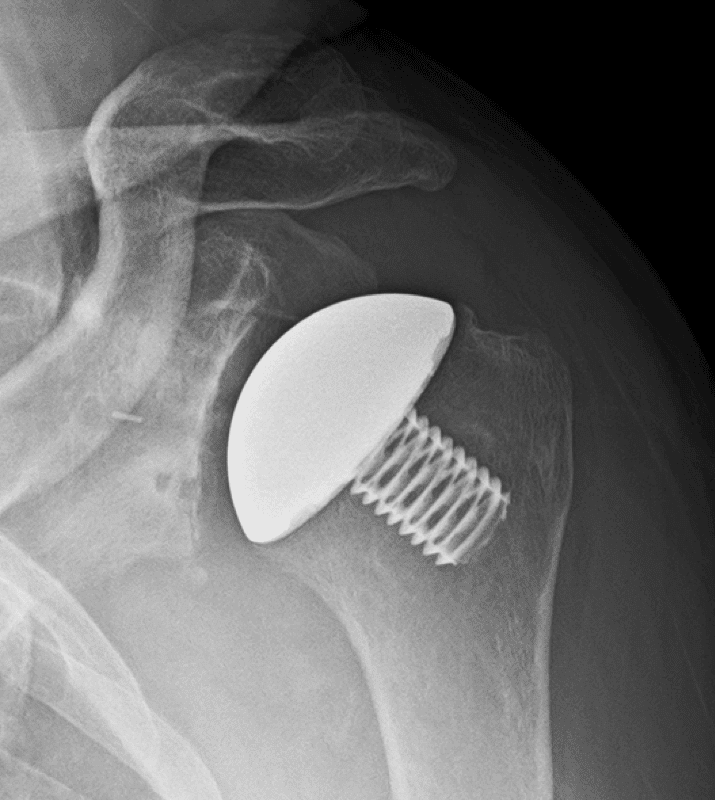

Arthrex, Eclipse